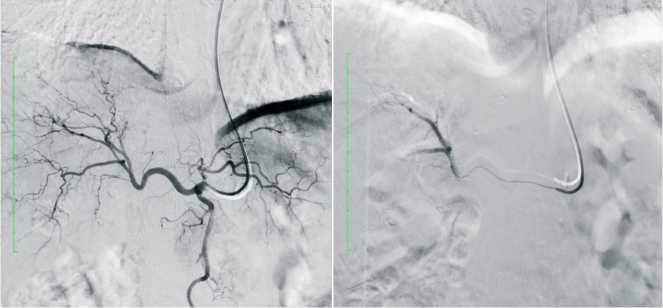

В рамках лекарственной терапии также применяли трансартериальную химиоэмболизацию (ТАХЭ). Перед процедурой на основе СКТ выполняли реконструкцию сосудов печени. Все операции проводили трансрадиальным доступом (через лучевую артерию) для снижения риска осложнений и ранней активизации пациентов. Использовали методику суперселективной катетеризации питающих артерий микрокатетерами. Этот подход обеспечивает точную доставку взвеси микроэмболов в опухоль, минимизируя риск окклюзии сосуда и нецелевой эмболии. Применяли калиброванные эмболы Hepasphere 50–250 мкм (25 мг), насыщенные концентрированным раствором доксорубицина. Взвесь вводили на скорости 1 мл/мин до достижения стойкого эффекта «стоп-контраст» в течение 7–8 сердечных циклов.

На предоперационном этапе пациентам выполняли трансартериальную химиоэмболизацию (ТАХЭ) для уменьшения размеров опухоли и повышения безопасности последующего вмешательства. С 2015 по 2025 гг. процедуру провели 34 пациентам (средний возраст 59,26±3,21 года; 13 мужчин, 21 женщина) с опухолями более 4 см (рис. 2).

Рис. 2. ТАХЭ S5 образования печени Fig. 2 TACE S5 liver lesions